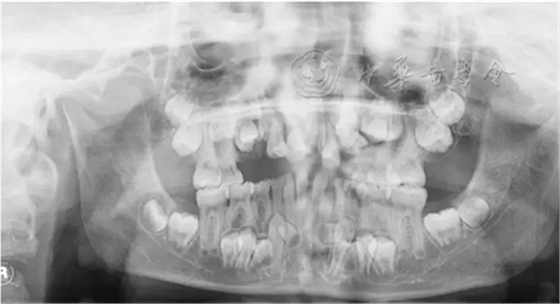

(1)疾病定義及口腔表現(xiàn):是一種罕見的以顱骨和鎖骨發(fā)育不良為主要特征的先天性骨骼系統(tǒng)發(fā)育異常綜合征,又稱Marie-Sainton綜合征,多為常染色體顯性遺傳。患者可表現(xiàn)鎖骨單側或雙側缺如,顱骨短大,囟門和顱縫寬、延遲閉合或不閉合,面骨較小,眼距寬,鼻梁塌陷。口腔表現(xiàn)為腭蓋高拱,部分患者表現(xiàn)為腭裂或腭黏膜下裂。乳牙萌出正常,除第一恒磨牙和其他個別牙外,多數(shù)恒牙不能正常萌出,影像學檢查可見牙胚發(fā)育遲緩,乳牙根吸收遲緩,頜骨內埋伏多顆額外牙(圖3)。有些癥狀較輕的患者可只表現(xiàn)為牙齒發(fā)育異常。

圖3 10歲顱骨鎖骨發(fā)育不全患兒曲面體層X線片,可見頜骨內多顆埋伏額外牙,恒牙胚發(fā)育遲緩,恒牙萌出障礙